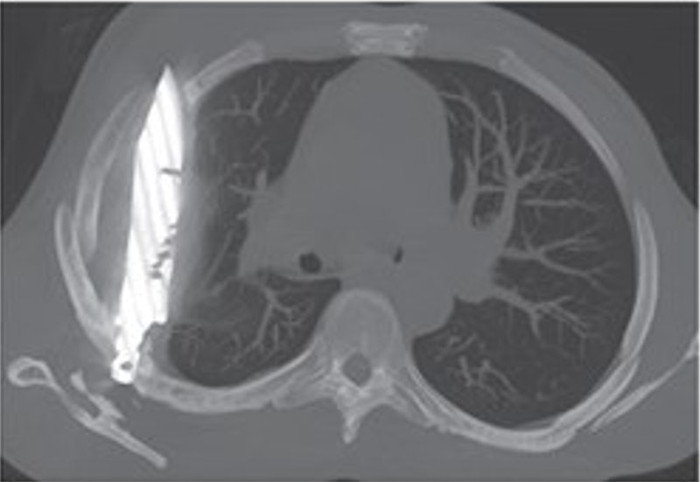

Trong quá trình thăm khám, người đàn ông nhớ lại một biến cố trong quá khứ: tám năm trước, anh từng tham gia một cuộc ẩu đả dữ dội, bị chém nhiều nhát vào mặt, lưng, ngực và bụng. Dù đã được điều trị, nhưng dường như có điều gì đó bị bỏ sót. Các bác sĩ quyết định chụp X-quang, và phát hiện sự thật gây sốc: một lưỡi dao lớn vẫn còn găm trong lồng ngực anh suốt tám năm qua.

Kết quả hình ảnh cho thấy lưỡi dao xuyên qua xương bả vai phải và nằm trong khoang ngực, nhưng may mắn không đụng chạm đến tim, phổi hay các cơ quan trọng yếu khác. Chính sự “ăn may” này đã giúp bệnh nhân sống sót mà không gặp biến chứng nghiêm trọng trong suốt thời gian dài. Chỉ đến khi cơ thể phản ứng bằng việc rỉ mủ từ vùng ngực, bí mật khủng khiếp mới được phơi bày.